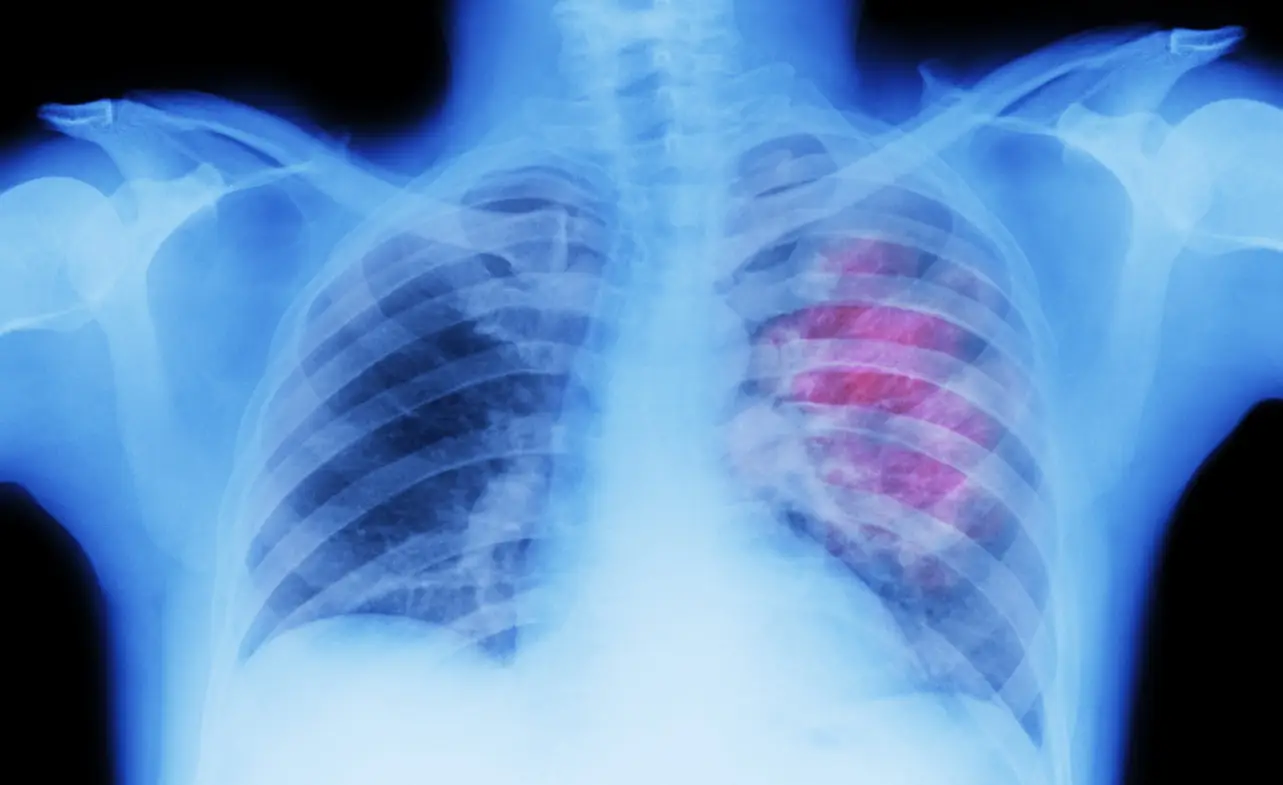

Stage 4 lung cancer is an advanced form of lung cancer that has spread to other parts of the body. It is also known as metastatic cancer and is considered the most advanced stage of the disease. At this stage, the cancer has typically spread to distant organs such as the liver, brain, or bones.

The symptoms of stage 4 lung cancer can vary depending on the location and extent of the spread. Common symptoms may include shortness of breath, persistent cough, fatigue, weight loss, and chest pain. The spread of cancer cells may also cause other symptoms such as headaches, seizures, or bone pain.